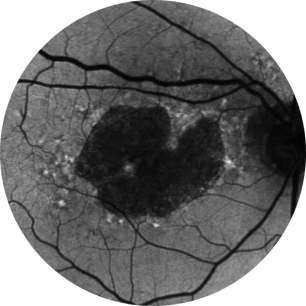

Baseline Year 1

BCVA 20/63+, GA Area 5.18 mm2

Baseline Year 2

BCVA 20/80-2, GA Area 10.39 mm2

Baseline Year 5

BCVA 20/200, GA Area 18.58 mm2

Images courtesy of David Elchenbaum, MD, Retina Vitreous Associates of Florida.

BCVA = Best-corrected visual acuity.